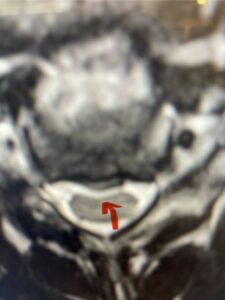

This 61-year-old female with a history of severe osteoporosis and a prior history of a laminectomy from l2-S1 with an L5-S1 instrumented fusion, presents with progressive low back pain and right lower extremity radiculopathy. MRI revealed a grade 1 L2-3 spondylolisthesis with severe stenosis mainly from severe right L2-3 facet joint hypertrophy which was compressing the right L3 descending nerve root. (Fig. 1). She had failed conservative management consisting of physical therapy and pain management with epidurals. She underwent an L1-3 revision laminectomy where we had to dissect a plane underneath the inferior aspect of the L2 lamina. We performed an instrumented fusion at L2-3 with special hydroxyapatite-coated screws to improve fixation to surrounding bone given here severe osteoporosis (Fig. 2) This worked out well and the patient had an uneventful recovery with relief of her leg pain.

Figures 1a: Sagittal and axial T2-weighted lumbar MRIs demonstrating a grade 1 L2-3 spondylolisthesis (red arrow) with severe stenosis secondary to right L2-3 facet hypertrophy (red arrow).

Fig 1b: Note the left L2-3 facet joint (blue arrow) is normal in size compared to the right (red arrow)